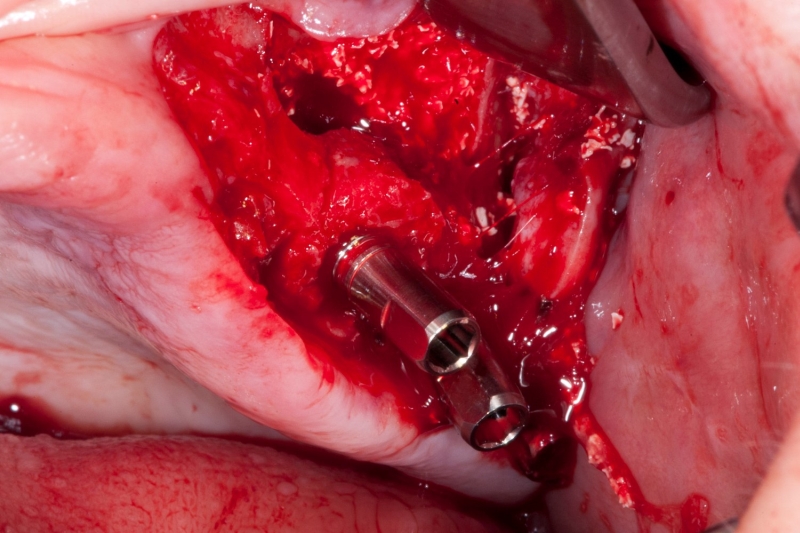

15/18 - Press-fit placement of maxgraft® bonering into the defect

Vertical augmentation & sinus lift with maxgraft® bonering - Dr. O. Yüksel and Dr. B. Giesenhagen